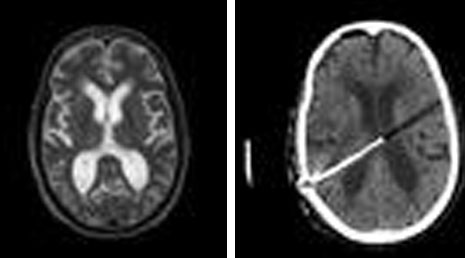

25. Cranial gunshot.